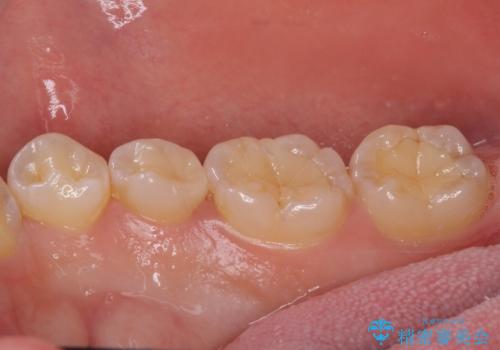

- 前歯のデコボコを強い咬みしめを気にして来院された患者様です。

インビザラインを用いて、前歯の叢生を解消するとともに、ディープバイトを改善していくこととしました。

ディープバイトが改善されたことで、顎への負担が軽減され、更には上顎前歯の突出感も改善することができました。

矯正治療後には欠けてしまった修復物をセラミックインレーにて修復治療しました。